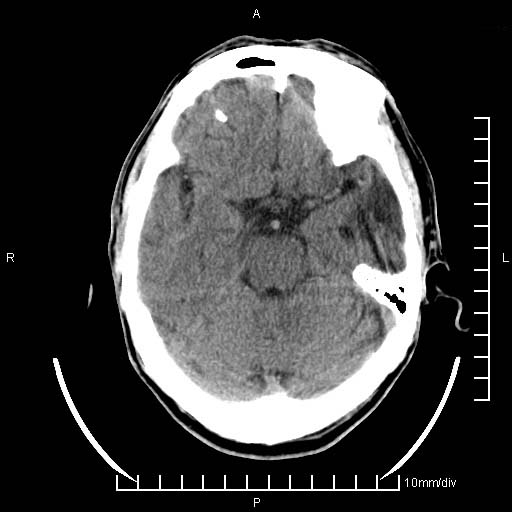

临床以双下肢浮肿,疼痛收治,无明显神经系统症状,既往无梗塞,出血病史。左颞叶见低密度灶,考虑什么?

无强化、 无占位、局部脑沟增宽, 软化灶吧。